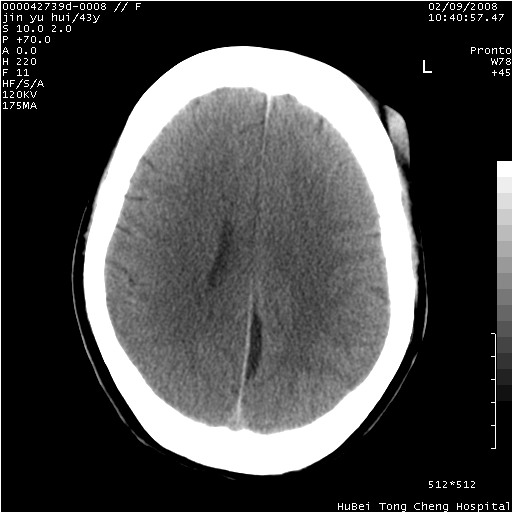

患者 女,43岁。头部外伤26天,经住院治疗,现头痛减轻。申请ct复查,了解颅内情况。

临床诊断:2级脑外伤。

颅脑ct轴位平扫(层厚、层距均为10mm),图像如下:

大脑镰左旁硬膜下血肿慢性期。

大脑镰左旁慢性硬膜下血肿.

左大脑镰旁硬膜下慢性血肿。

是不是应该为:大脑镰左旁硬膜下血肿吸收期更妥当些;